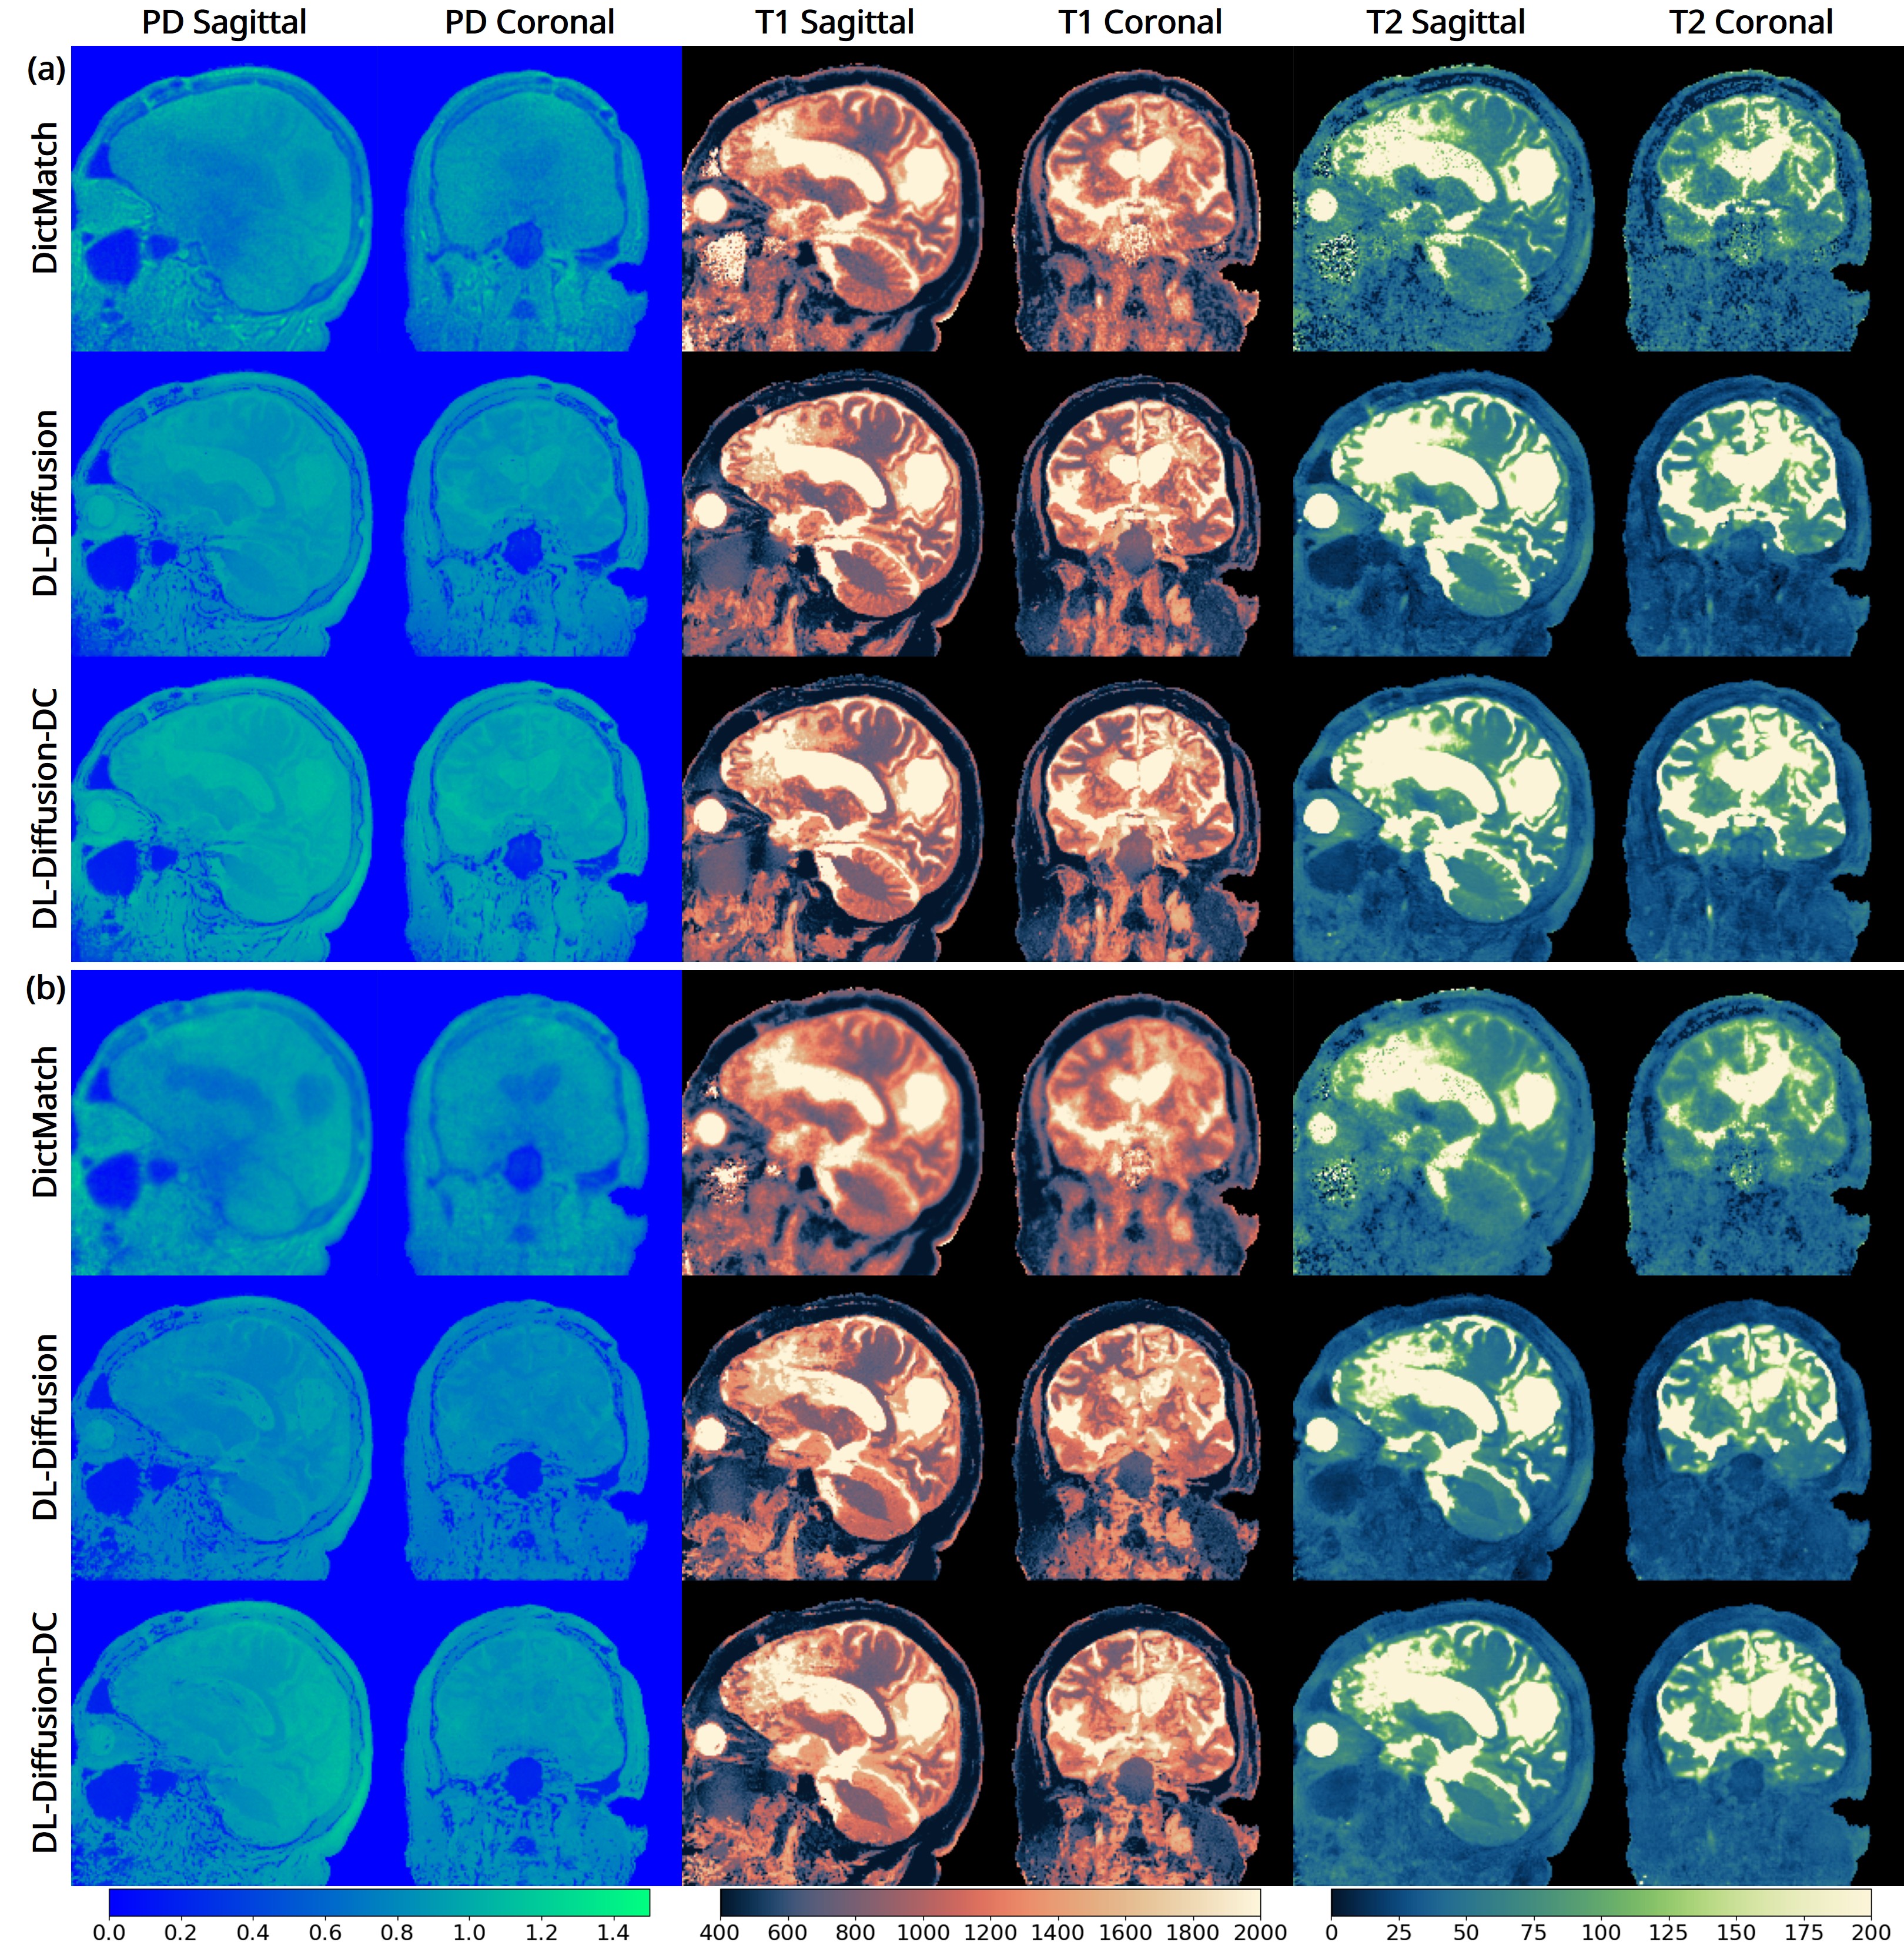

The 3D fast silent multi-parametric mapping sequence with zero echo time (MuPa-ZTE) is a novel quantitative MRI (qMRI) acquisition that enables nearly silent scanning by using a 3D phyllotaxis sampling scheme. MuPa-ZTE improves patient comfort and motion robustness, and generates quantitative maps of T1, T2, and proton density using the acquired weighted image series. In this work, we propose a diffusion model-based qMRI mapping method that leverages both a deep generative model and physics-based data consistency to further improve the mapping performance. Furthermore, our method enables additional acquisition acceleration, allowing high-quality qMRI mapping from a fourfold-accelerated MuPa-ZTE scan (approximately 1 minute). Specifically, we trained a denoising diffusion probabilistic model (DDPM) to map MuPa-ZTE image series to qMRI maps, and we incorporated the MuPa-ZTE forward signal model as an explicit data consistency (DC) constraint during inference. We compared our mapping method against a baseline dictionary matching approach and a purely data-driven diffusion model. The diffusion models were trained entirely on synthetic data generated from digital brain phantoms, eliminating the need for large real-scan datasets. We evaluated on synthetic data, a NISM/ISMRM phantom, healthy volunteers, and a patient with brain metastases. The results demonstrated that our method produces 3D qMRI maps with high accuracy, reduced noise and better preservation of structural details. Notably, it generalised well to real scans despite training on synthetic data alone. The combination of the MuPa-ZTE acquisition and our physics-informed diffusion model is termed q3-MuPa, a quick, quiet, and quantitative multi-parametric mapping framework, and our findings highlight its strong clinical potential.💡 Summary & Analysis